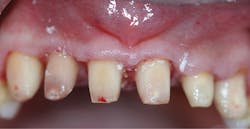

Once local anesthesia was achieved, the crowns were removed. Pulp exposures were noted in all teeth, necessitating root canal therapy (figure 3). Once the six teeth had received root canal therapy, the access openings were restored with a flowable, dual-curing, nano-hybrid core build-up material (Grandio Core Dual Cure, Voco). The teeth were prepared to correct margins while respecting surrounding periodontal structures. In order to allow the inflamed soft tissue to heal, a provisional “one-unit” bridge was fabricated and allowed to remain for six weeks (figure 4). A cold-cure composite provisional material was used (Structur 3, Voco), providing an elastic phase and allowing easy removal from the prepared teeth. The high gloss offered an ideal margin for the healing of inflammatory soft tissue, and elevated compressive strength and fracture resistance meant the patient could function in the provisional for longer periods of time.

Figure 4: Provisional “one-unit” bridge